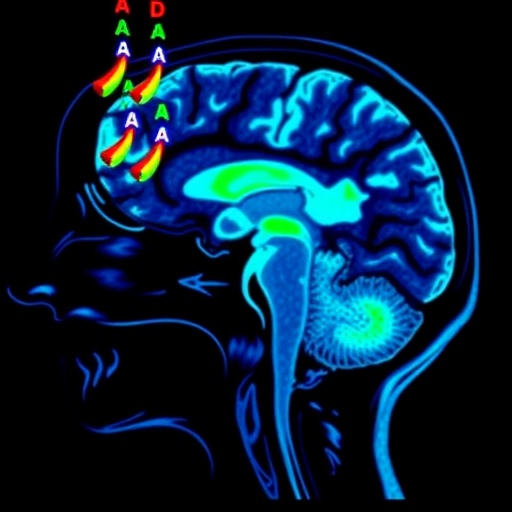

The core technological innovation lies in the application of susceptibility-weighted imaging (SWI) and diffusion magnetic resonance imaging (dMRI) to detect microstructural and iron-related alterations in strategic brain regions. SWI exploits variations in magnetic susceptibility to accentuate iron accumulation, a pathological hallmark of Parkinson’s disease, especially in the substantia nigra. Meanwhile, dMRI measures the diffusion of water molecules along neuronal pathways, revealing subtle microstructural disruptions that precede gross anatomical changes.

A cohort of patients diagnosed with iRBD underwent comprehensive MRI screening, with follow-up clinical assessments spanning several years. The imaging data unveiled distinct patterns of increased iron deposition and disrupted diffusion metrics consistent with nigrostriatal degeneration in those who eventually manifested Parkinsonism. Notably, these biomarkers appeared well before traditional motor symptoms emerged, illustrating the power of this approach to detect subclinical disease processes.

This study also highlights the critical role of iron metabolism dysregulation in the pathogenesis of Parkinsonism. Iron accumulation in the substantia nigra is both a diagnostic marker and a potential contributor to oxidative stress and neuronal death. By mapping these variations in vivo with SWI, researchers provide direct evidence correlating iron burden with disease onset among vulnerable individuals.

The diffusion MRI findings complement this by exposing microstructural impairments within the nigrostriatal pathways, indicating demyelination, axonal injury, or neuronal loss at stages traditionally considered presymptomatic. These changes underscore the silent progression of neurodegeneration and emphasize the urgent need for tools capable of capturing these early signals.